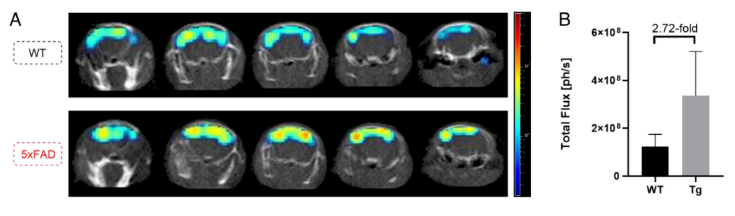

在小鼠的3D腦成像研究中,作者發(fā)現(xiàn)信號可達(dá)小鼠腦部深層0.5 cm處(圖4)。并且,對比野生型和AD小鼠不同位置的3D腦成像信號強(qiáng)度均有不同,差別可達(dá)2.72倍,相較于二維腦成像的信號差別(1.8倍)有所增加。所以,該方法不僅可以區(qū)分健康和AD小鼠,同時也提高了定量分析結(jié)果(圖5)。

圖5. 三維腦成像區(qū)分健康和疾病小鼠。圖片來源:PNAS